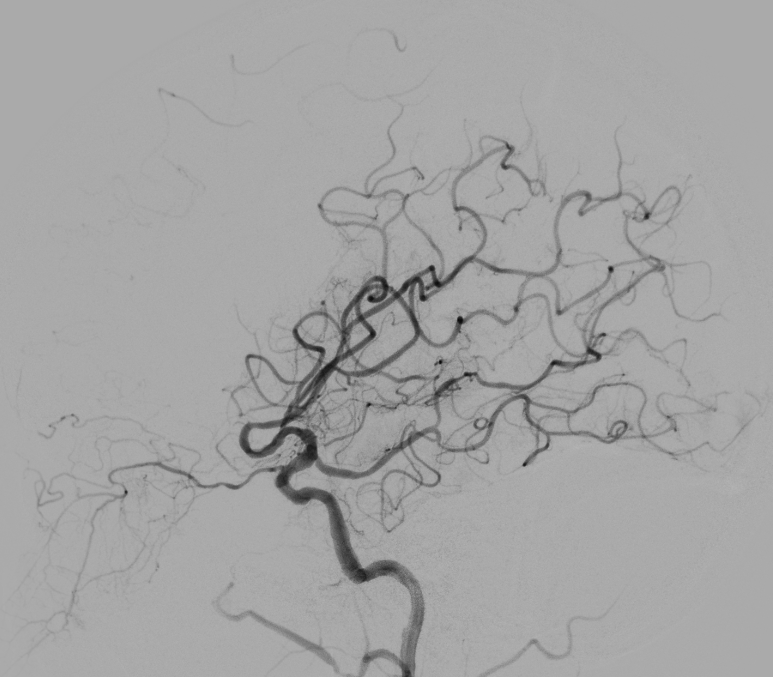

5 分钟后,张女士被推进介入手术室,急诊脑血管造影进一步确认了血管闭塞情况。

10 分钟后,手术顺利完成,堵塞血管成功开通,濒临坏死的脑细胞被及时 “救回”,张女士的病情得到了有效控制。

而取栓手术,就是医生通过微创的方式,直接把堵在血管里的血栓取出来,快速打通被堵塞的 “生命河道”,拯救濒临死亡的脑细胞。